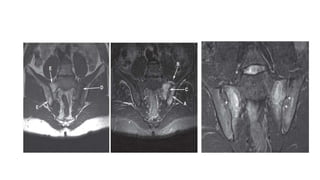

• Ultrasound or MRI of entheses

• MRI of the sacroiliac joints and spine

• Xray SI joint:

irregularity and loss of cortical margins

widening of the joint space

Subsequently sclerosis, joint space narrowing and fusion